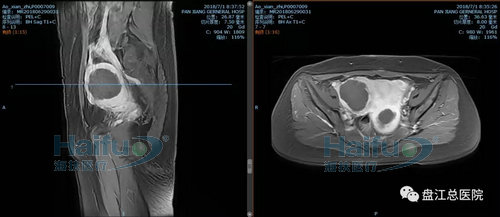

我院案例1:患者敖XX,44歲,多發性子宮肌瘤患者。

因經期延長1+月,發現盆腔包塊12+天入院。患者于2018-6-29在我院行高強度聚焦超聲消融治療(HIFU)。在鎮靜鎮痛狀態下,治療過程中未訴有特殊不適,安靜休息。本次治療時間70min。

術前后壁及右側壁肌瘤增強,見病灶明顯強化

術后后壁及右側壁肌瘤增強,見病灶內已無強化,病灶發生凝固性壞死